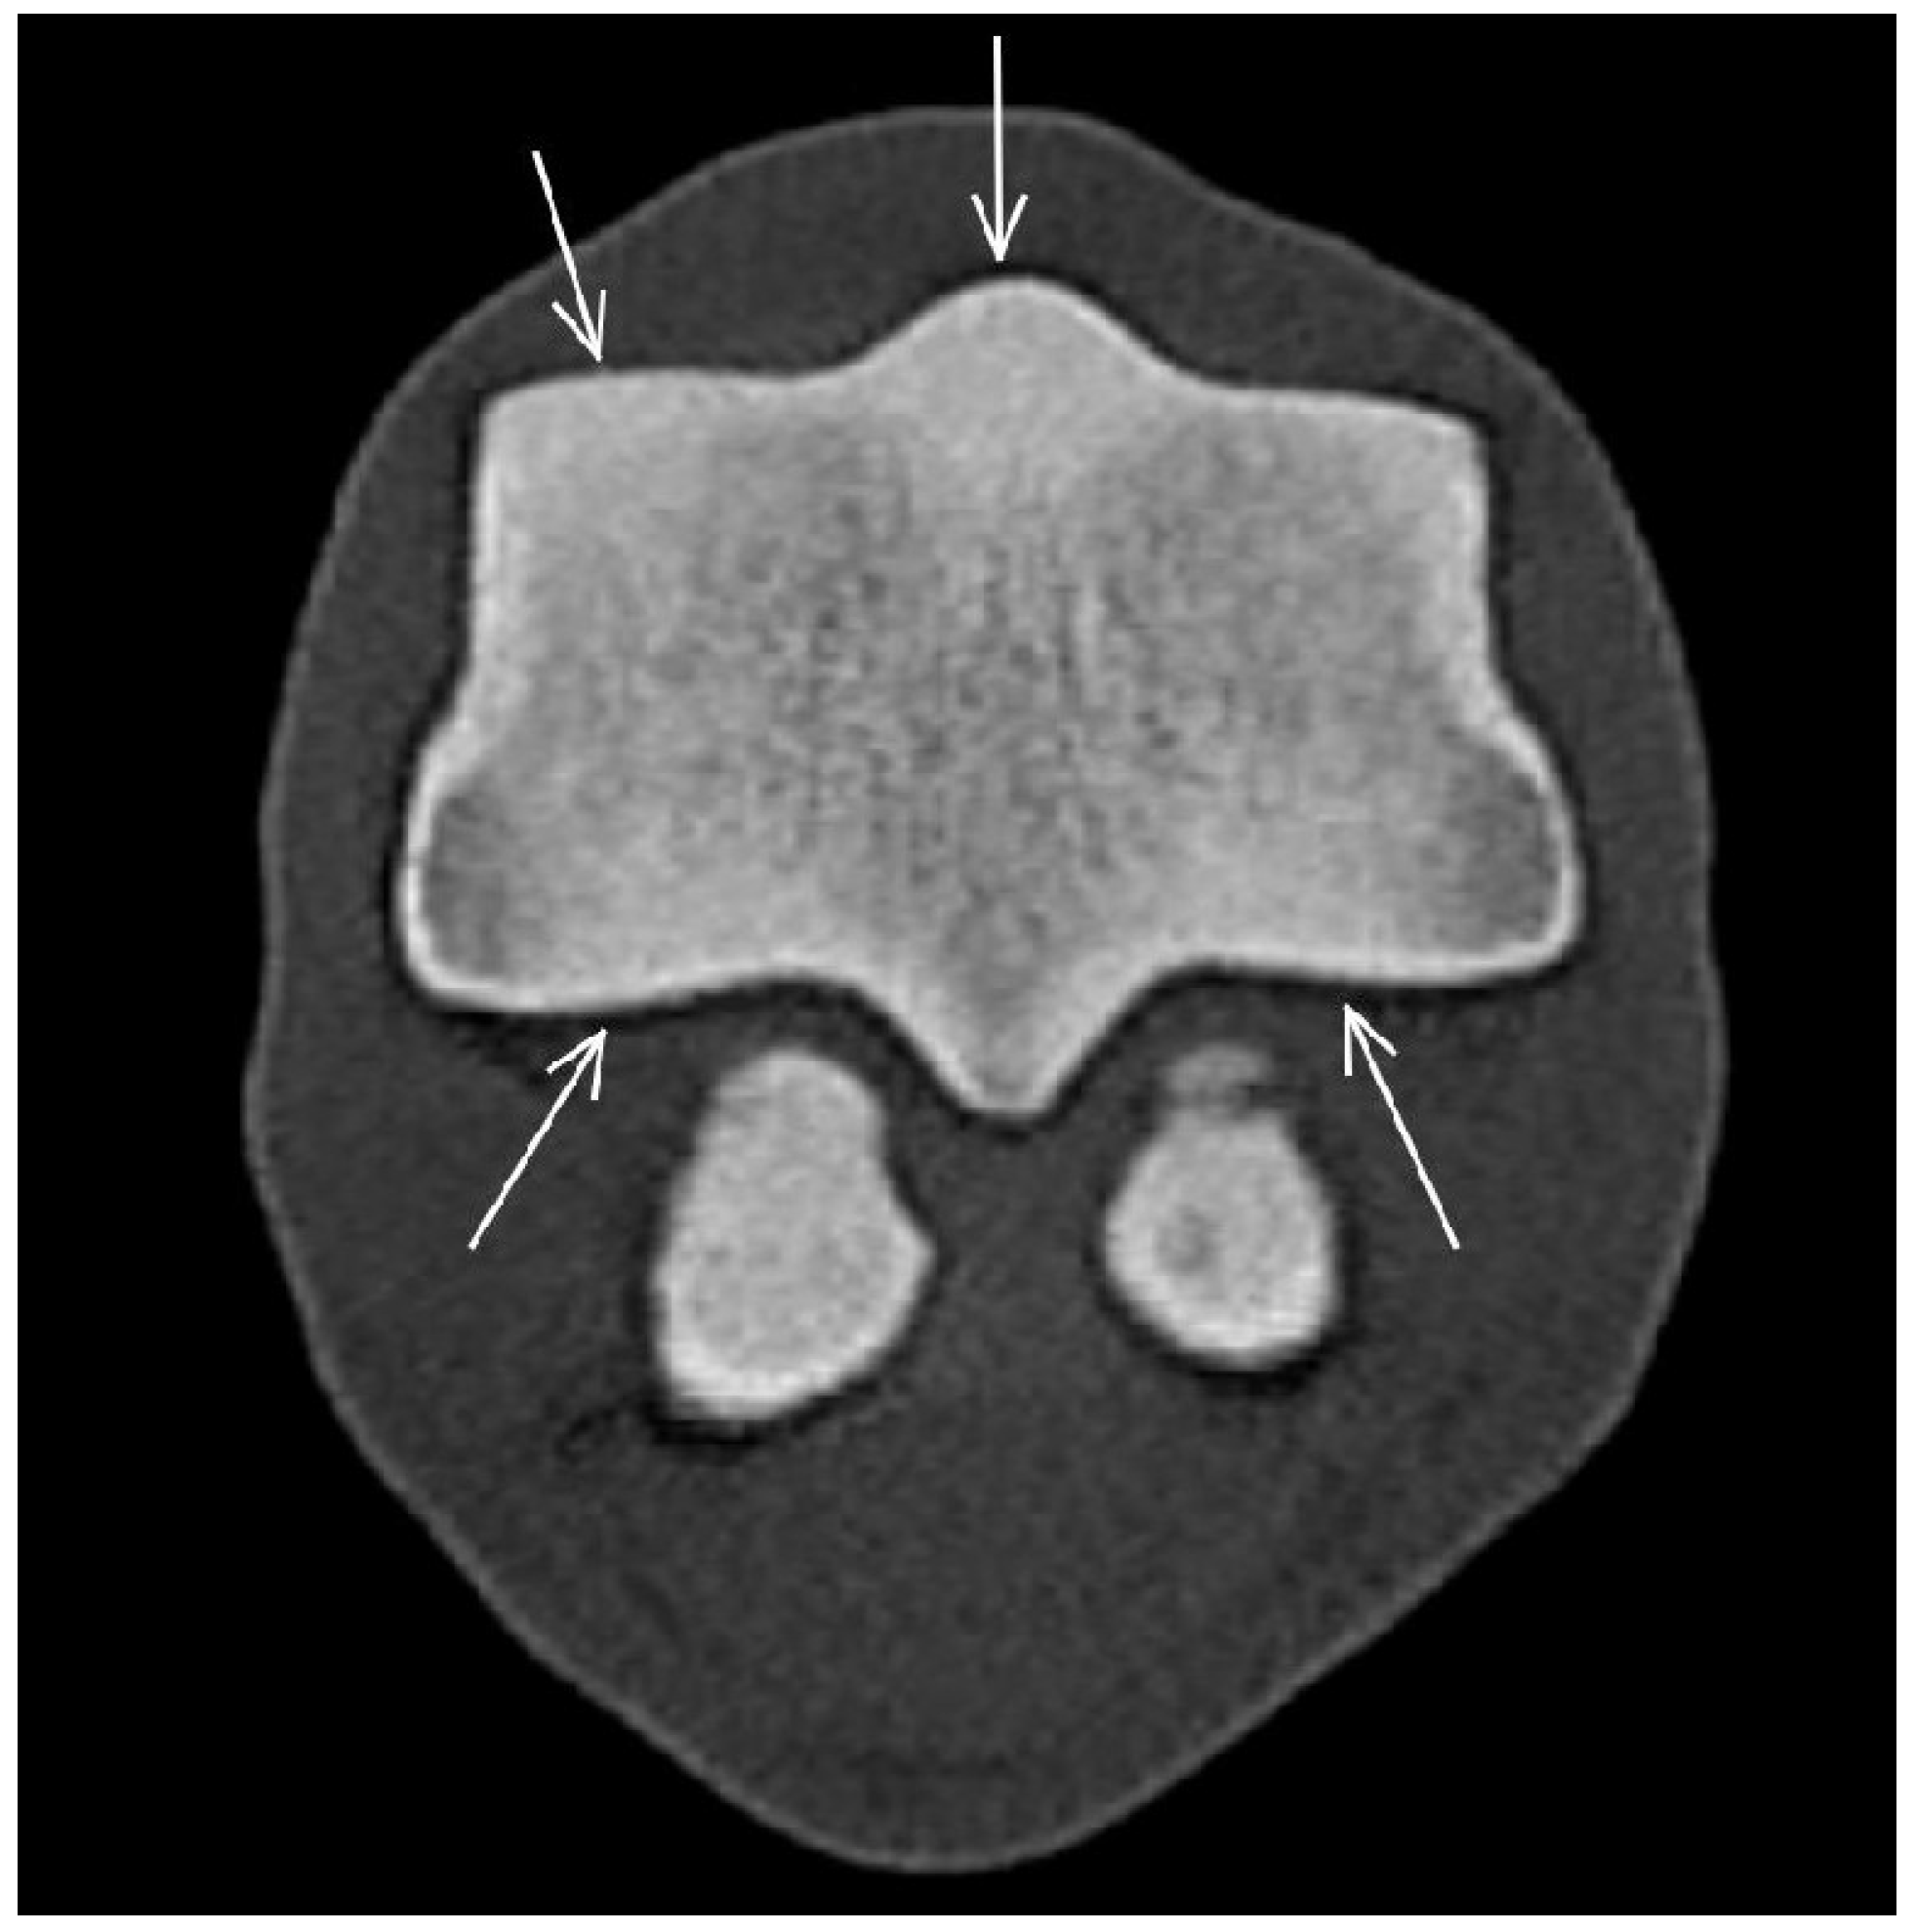

3.3. The Proximal Sesamoid Bones (PSBs)

| Proximal sesamoid bone Medial/Lateral | |||

| Prominent vascular channels Thickening of axial/abaxial compact bone Increased attenuation in trabecular bone Modelling | Thickening of axial/abaxial compact bone Decreased signal intensity in trabecular bone Modelling | Prominent vascular channels Modelling | |